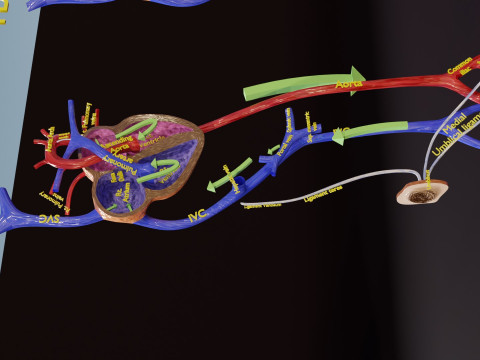

A blend model of brain along with its covering layers (meninges), skull bone and scalp labelled in detail and anatomically precise. The parts depicted are white, gray, pia, arachnoid, dura, bone, skin, fat, aponeurosis, periosteum, falx cerebri and more.